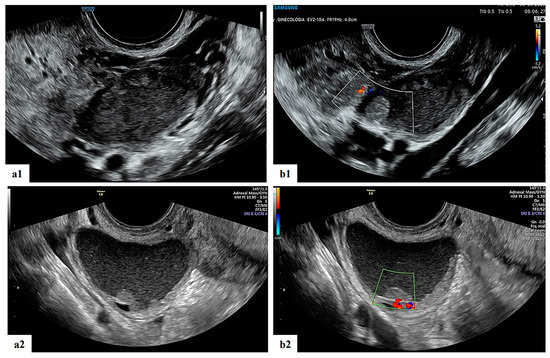

- Mascilini, F.; Moruzzi, C.; Giansiracusa, C.; Guastafierro, F.; Savelli, L.; De Meis, L.; Epstein, E.; Timor-Tritsch, I.E.; Mailath-Pokorny, M.; Ercoli, A.; et al. Imaging in gynecological disease. 10: Clinical and ultrasound characteristics of decidualized endometriomas surgically removed during pregnancy. Ultrasound Obstet. Gynecol. 2014, 44, 354–360. [Google Scholar] [CrossRef]

- Moro, F.; Mascilini, F.; Pasciuto, T.; Leombroni, M.; Li Destri, M.; De Blasis, I.; Garofalo, S.; Scambia, G.; Testa, A.C. Ultrasound features and clinical outcome of patients with malignant ovarian masses diagnosed during pregnancy: Experience of a gynecological oncology ultrasound center. Int. J. Gynecol. Cancer 2019, 29, 1182–1194. [Google Scholar] [CrossRef]

| Presence of papillary projections | 4 |

| Number of papillary projections 1 2 3 | 1/4 2/4 1/4 |

| Papillation contour Irregular Smooth | 1/4 3/4 |

| Papillation flow Present Absent | 2/4 2/4 |

| Height of the largest papillary projection (mm) (range) | 7.5 (3–13) |